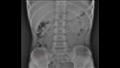

وكشفت فحوصات الأشعة السينية لصدر وبطن الطفل عن وجود قلم رصاص عالق في معدته، لذا أخبره الطبيب بالإكثار من السوائل، ، ولم يسمحوا له بتناول أي شيء سوى الموز لتسهيل عملية إزالة القلم من أمعائه.

أظهرت الأشعة السينية لاحقا أن قلم الرصاص تحرك من المعدة ليصل إلى "اللفائفي الأعوري"، وهو صمام عضلي يفصل بين الأمعاء الدقيقة والغليظة.